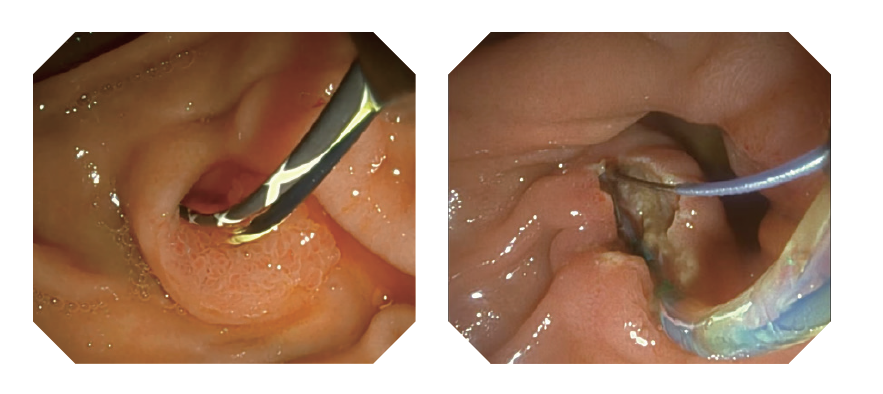

15° žiūrėjimo kampas atgal kartu su plačiu regėjimo lauku padidina pageidaujamą endoskopinę vizualizaciją.

Naudojant didelės raiškos vaizdus ir turimą VlST* technologiją, patobulinti gleivinės raštai gali padėti identifikuoti papilvę.

*VIST: Įvairiapusė išmanioji dažymo technologija